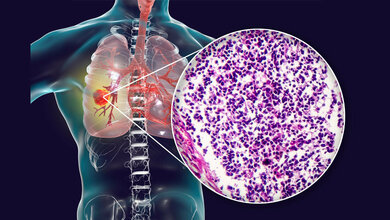

Nach wie vor ist Krebs eine häufige Diagnose. Etwa 500.000 Neuerkrankungen sind pro Jahr in Deutschland zu verzeichnen.

Allerdings macht der Fortschritt auch vor diesen Erkrankungen nicht Halt. Kaum ein anderes Fachgebiet der Medizin ist von solch einer Explosion des Wissens gekennzeichnet wie die Onkologie.